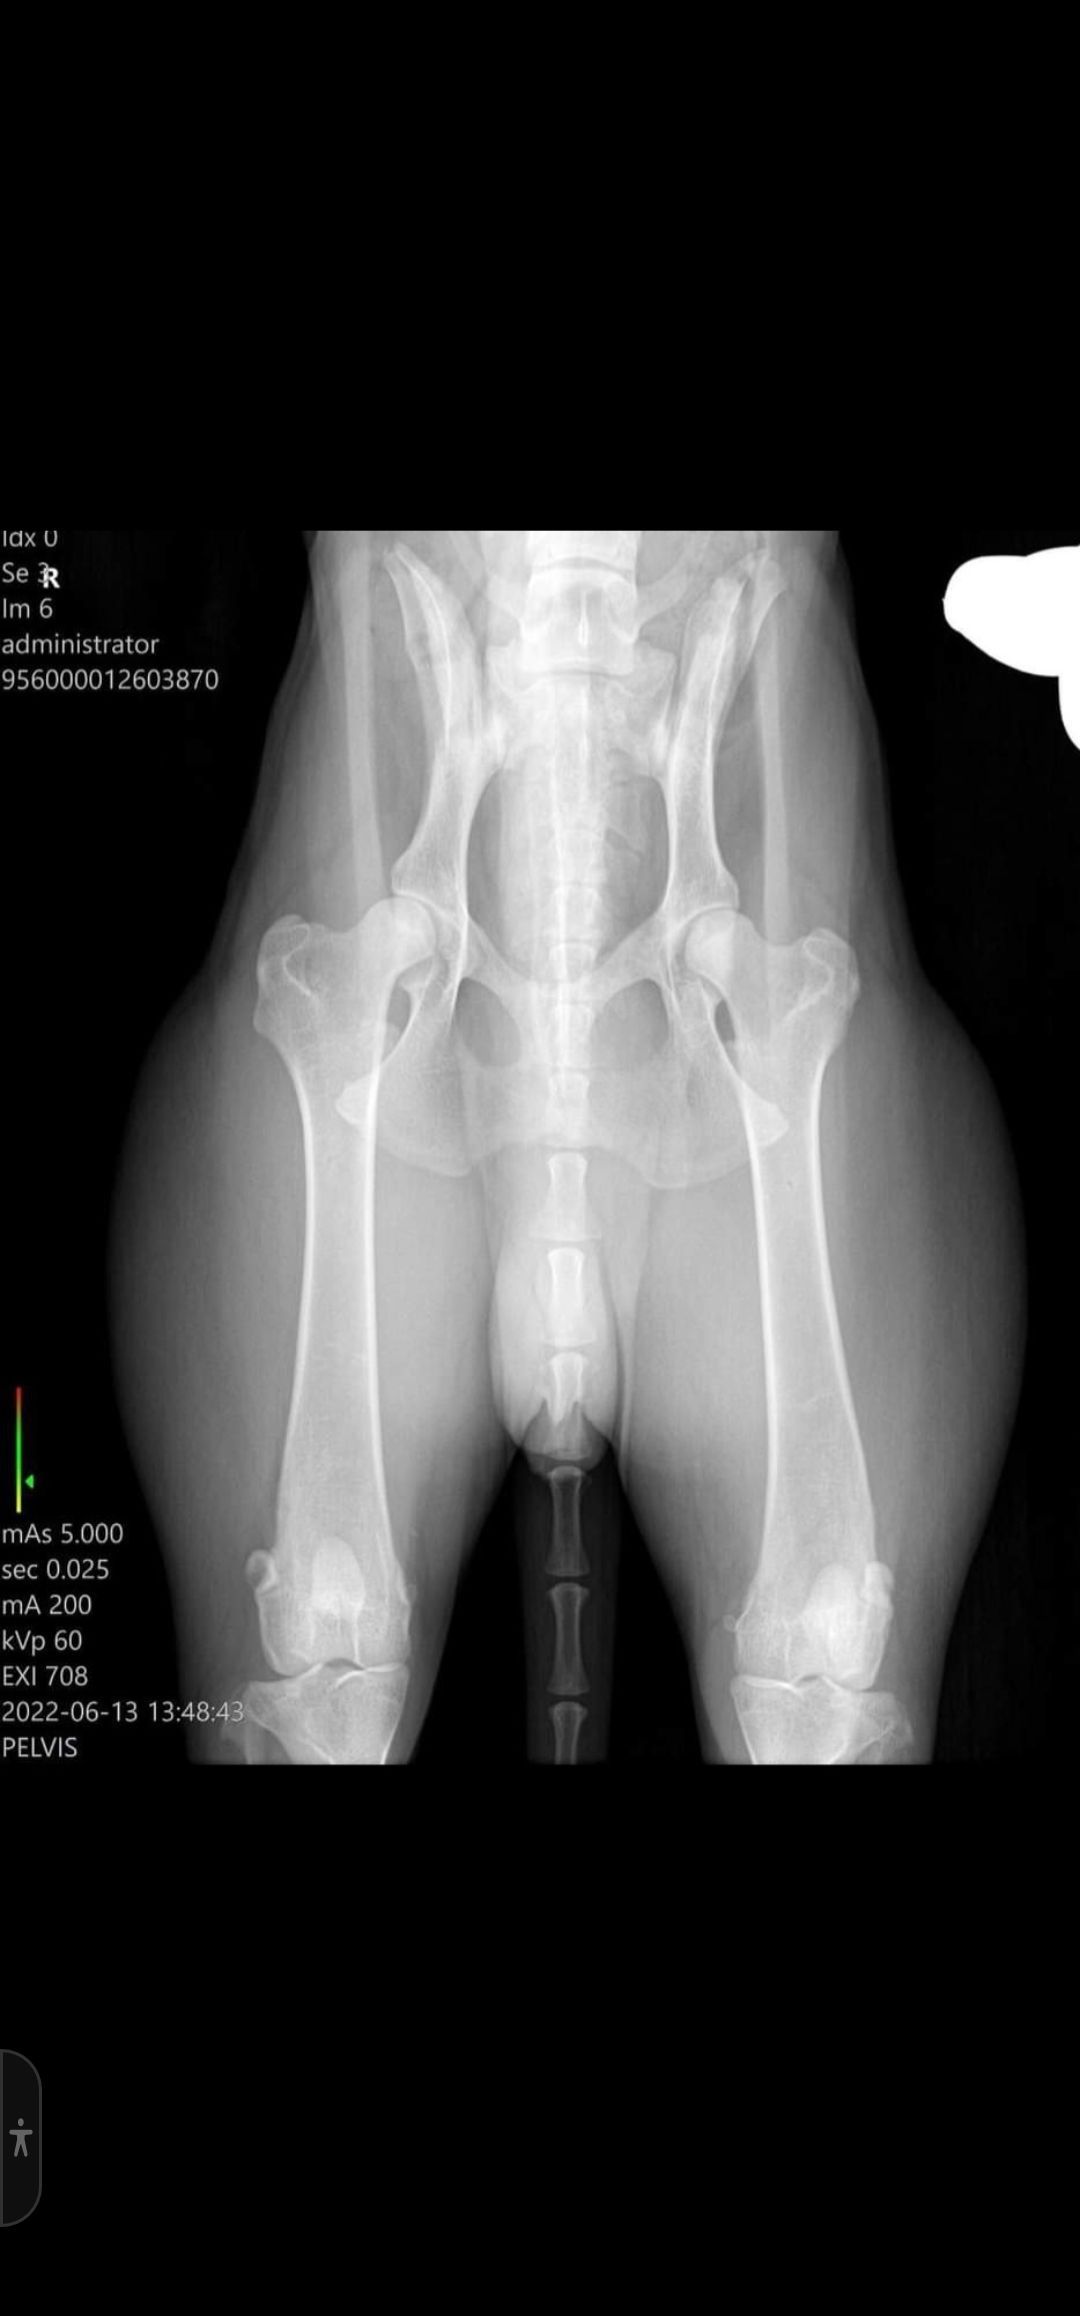

Bild 2 Junghund 6 Monate, die Knochen sind nun zusammen gewachsen